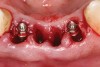

Figure 4  Implants were placed without flap elevation.

Figure 4

Figure 5  Tapered implants with conical transgingival abutments and temporary cylinders in place.

Figure 5

Preoperatively, 1 g of amoxicillin was administered. Using local anesthesia (lidocaine 1:100,000 epinephrine), extractions of teeth Nos. 23 to 26 were performed without raising a flap and with gentle luxation to preserve the remaining facial osseous plate. The sockets were curetted prior to implant placement. A vacuum-formed surgical guide, fabricated based on a diagnostic wax-up of the desired tooth positions for the subsequent fixed prosthesis, was used during implant placement. Osteotomies were performed at site Nos. 23 and 26 and positioned toward the lingual aspects of the sockets (Figure 3 and Figure 4). Two tapered implants (OsseoTite™ 313, BIOMET 3i™, www.biomet3i.com) measuring 3.25 mm x 13 mm were placed. Conical prosthetic abutments (3-mm height) were used to facilitate joining the two implants in a screw-retained FPD (Figure 5). A laboratory-processed acrylic-resin provisional restoration was altered to allow connection to the temporary cylinders. The provisional was placed into the vacuum-formed surgical guide that was now used to maintain the provisional in the correct 3-dimensional position (Figure 6) while being attached to the temporary cylinders with acrylic resin intraorally. Once a sufficient amount of acrylic resin was placed to secure the cylinders to the provisional, it was removed from the mouth and its contours were completed at the laboratory bench (Figure 7). The two central incisor sockets were grafted with small-particle allograft material (Puros® Allograft, Zimmer Dental, www.zimmer.com) to maintain the gingival architecture beneath the two ovate pontics (Figure 8). The provisional restoration was inserted and the screws were tightened to 20 Ncm of torque.